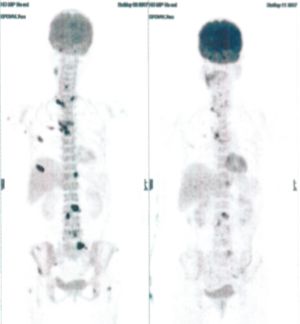

Below are some of the cases, from more than 80 cases we have treated so far with good results. When reading the PET/CT scans, the picture on the left is before treatment, and the picture on the right is after treatment. The intensity of black represents the activity of the cancer, but some black areas are not cancer: brain, heart, radioactive urine in bladder. For the heart, the intensity of black depends on the number of hours of fasting: if more than 10 hours, the heart is not even black, but if fasting is less than 6 hours, it is very black. The intensity of black in the brain can be variable in different scans depending on the brain activity at the time of the scan. The intensity of black in the radioactive urine can also be variable due to the hydration of patients and the time of injection of diuretic.

CASE NO: 3 (PROSTATE CANCER)

A middle-aged man with castration resistant prostate cancer, having failed all currently available cancer treatment, was very weak, and getting worse every day. The PET/CT scan showed he had massive bone metastases. After a few treatment, all the bone metastases went into remission. About 6 months later, he is still in remission.

CASE NO: 4 (PROSTATE CANCER)

A middle-aged man with castration resistant prostate cancer and massive bone metastases, failed all currently available cancer treatment, including with the new and expensive drug XTANDI. After a few treatment, most of the bone metastases went into remission, and the remaining ones are less active. Treatment will continue. Cases no: 3 and 4 show that terminal prostate cancer today can be cured with our new cancer treatment.